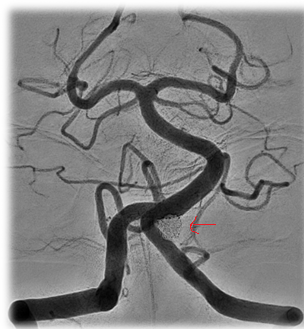

![]() Figure 3: Final angiographic result. Note the red arrows showing the final coil mass. |

![]() Figure 2: Intraprocedural Images of First Atlas Case. Note the red arrows indicating the radiopaque markers on either end of the stent. |